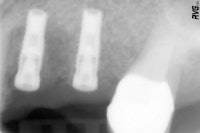

Figure 6 (bottom): Radiograph to control the implants after implantation.

The Spread-Condense screws were inserted in ascending order up to size 3 with the ratchet. Alternatively, a mechanical wrench was used for rotary insertion; however, this was preceded by the manual wrench (figure 5). Two Wital implants (Wieland Dental) were inserted with primary stability without further chip-producing preparation (figure 6). The treatment concluded with the augmentation of the autologous vestibular bone in tooth 24 and the filling of the defect bone up to the terminal molar.